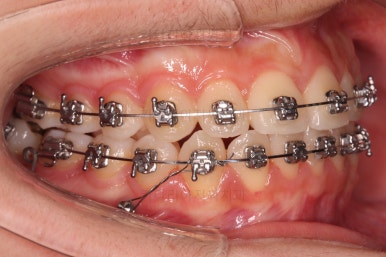

이번에 사용한 장치는 엠파워메탈이라고 하는 자가결찰(철사를 잡아주는 뚜껑이 달려있는) 메탈(금속성분) 장치입니다.

매우 장점이 많으나 심미성과 재료 제작비용 때문에 상대적으로 저렴한(이것도 장점일 수 있죠) 장치입니다.

장치를 부착했을 때 입이 나오는 느낌, 웃을 때 보이는 느낌은 참고해 주세요.

쓰러져 있던 치아도 장치를 부착하여 일으켜 세워주는 힘을 줍니다.

자칫 나머지 치열이 틀어질 수 있기 때문에 아랫니에는 부산교정 미니스크류를 이용해서 반작용을 막아줍니다.

점점 뒤쪽 치아가 바로 일으켜세워지고 있네요.